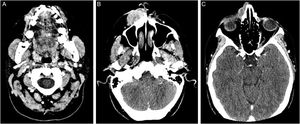

A análise imuno‐histoquímica revelou marcadores positivos para citoqueratina 5/6 e p63; BerEp4, EMA e fator XIIIa focalmente positivos; com adipofilina, receptor de andrógeno e CEA negativos (fig. 4), confirmando a origem escamosa da neoplasia. A tomografia computadorizada da face e do pescoço evidenciou lesão expansiva sólida com ampla ulceração superficial e intenso realce heterogêneo pelo meio de contraste, estendendo‐se pela asa nasal e região maxilar direitas. Notada destruição óssea nasal e do seio maxilar direito, com proximidade à órbita direita e à raiz dentária do canino superior direito (fig. 5). Nenhuma metástase foi encontrada nos exames de imagem. Considerando a extensão da lesão, as equipes de oncologia e cirurgia de cabeça e pescoço optaram por realização de quimioterapia neoadjuvante e avaliação posterior de abordagem cirúrgica.

(A) Tomografia computadorizada da face e do pescoço: proximidade da neoplasia à raiz dentária do canino superior direito. (B) Tomografia computadorizada da face e do pescoço: lesão expansiva sólida com ampla ulceração superficial, estendendo‐se pela asa nasal e região maxilar direita, medindo 3,6×1,9×4,5cm. (C) Tomografia computadorizada da face e do pescoço: destruição óssea nasal e extensão superior, próxima à órbita direita. O tumor apresenta realce intenso e heterogêneo ao meio de contraste